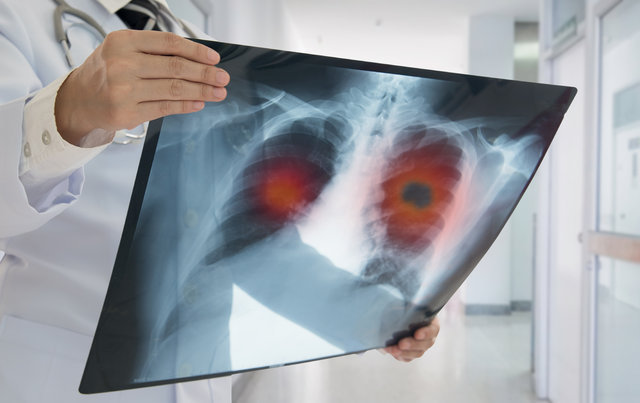

Akciğer kanseri her yıl dünyada 1.6 milyon kişinin yaşamını tehdit ediyor. Hem erkek hem de kadınlarda kanserden yaşam kaybının önde gelen nedeni olarak gösterilen hastalık, 45 yaş altında nadiren ortaya çıkarken, 50 yaş üzerinde risk artıyor.

Yapılan araştırmalar birçok faktörün akciğer kanserinin gelişimine katkıda bulunduğunu gösteriyor.

Göğüs Hastalıkları Uzmanı Prof. Dr. Necla Songür, “17 Kasım Dünya Akciğer Kanseri Günü” nedeniyle, akciğer kanseri ile doğrudan ilişkili olabilecek risk faktörleri ve akciğer kanserinden korunmanın yolları hakkında bilgi verdi.